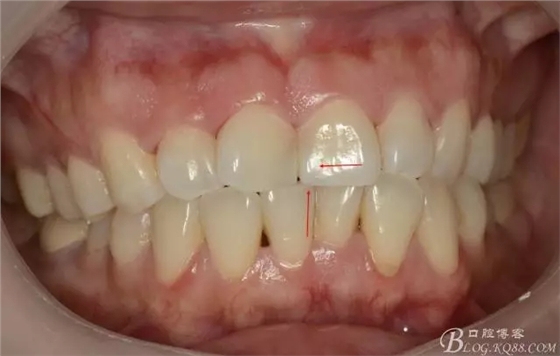

1)術(shù)前照

術(shù)后即刻照,發(fā)現(xiàn)兩中切牙近中切角區(qū)明顯發(fā)白??

術(shù)后即刻:

(箭頭處所指,可見明顯脫礦發(fā)白!)